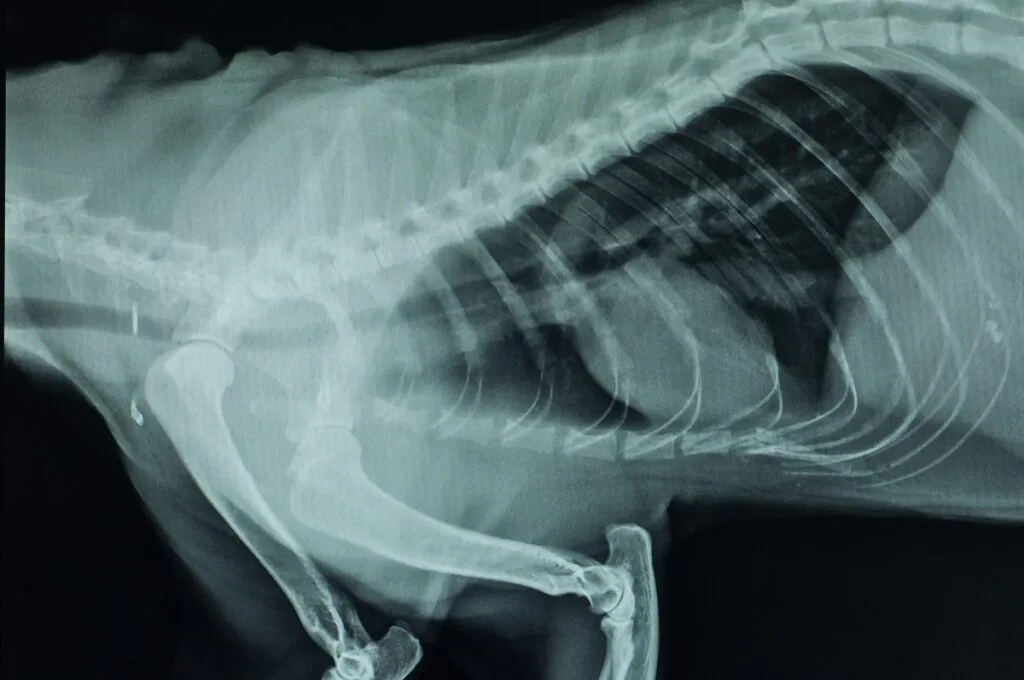

Quando a situação clínica do seu patudo estiver estabilizada o veterinário vai examinar as vias respiratórias. Para tal pode usar um traqueoscópio ou fazer radiografias. No entanto, para examinar a traqueia e verificar se existe um colapso é necessário fazer uma traqueoscopia.